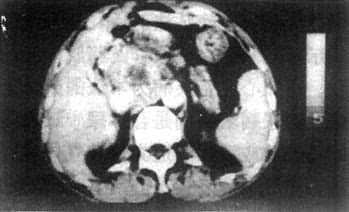

3.胰腺癌 CT表现为胰腺局部增大,呈肿块状隆起或呈分叶状增大。肿瘤的密度常与胰腺的密度相等,但其中常有坏死或液化而形成低密度区。增强扫描肿瘤常不增强或略增强,而正常胰实质增强明显,从而使肿瘤得以识别。这种密度的改变比看到肿块何能更重要。胰头癌侵犯、压迫胆总管引起梗阻性黄疸时,CT显示胆总管以上肝内外胆管扩张而胰头处胆总管突然狭窄、中断或变形。因此在梗阻性黄疸患者,必须沿扩大的胆管向下查寻,找到狭窄中断的位置。胰头部癌发生于钩突或累及钩突,若扫描层面不够低可能遗漏病变。胰头癌常阻塞胰管近段而使胰管扩大,表现为胰体中部偏前的管状低密度带,这也是胰头癌的一个重征象。胰腺癌进展,可使胰周脂肪层消失,邻近血管可被推移甚至包埋。肝门和腹膜后可出现淋巴结增大(图4-3-18)。

图4-3-18 胰腺癌CT表现

上图:CT平扫示胰头增大

下图:增强扫描,肿块不均匀强化,

中心有不规则低密度区